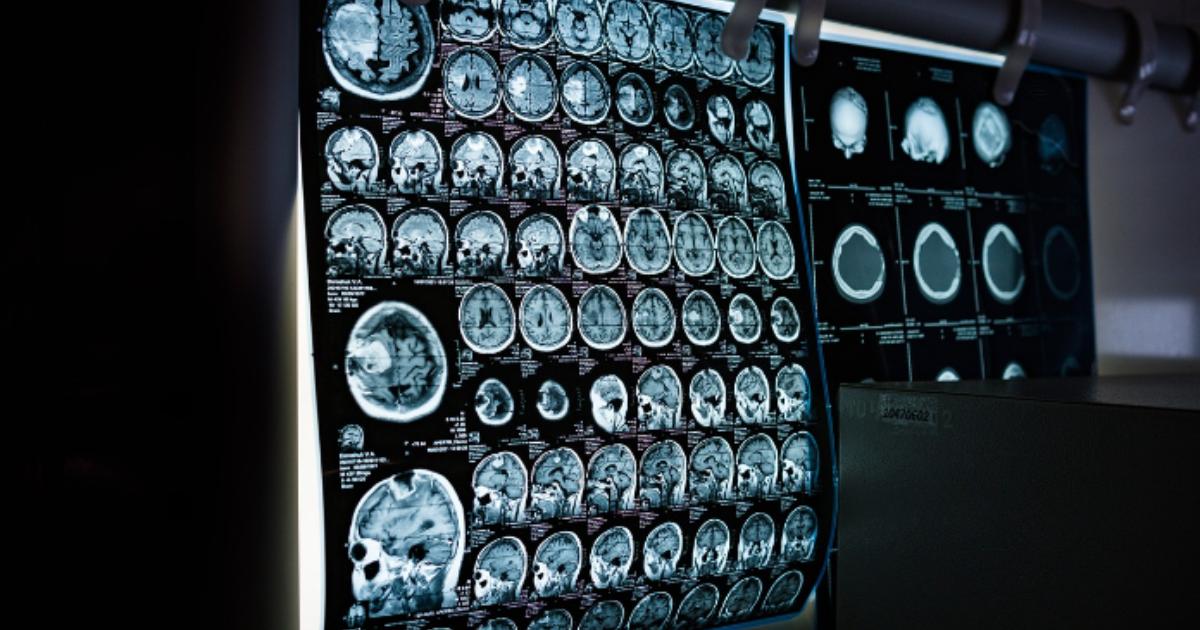

Magnetic Resonance Imaging (MRI)

MRI is a bit different because it uses strong magnets and radio waves instead of X-rays. This technique is fantastic for getting detailed images of soft tissues like the brain, spinal cord, and muscles. Since MRIs don’t use radiation, they’re safer for repeated use. Doctors often use MRIs to diagnose things like brain injuries, spinal cord issues, and joint problems.

Accuracy and Precision in Diagnosis

Medical imaging techniques are incredibly accurate and precise, which helps doctors make correct diagnoses without needing to perform invasive surgeries. High-resolution images from MRIs or CT scans provide detailed information about abnormalities, making it easier to diagnose complex conditions like brain tumors or heart diseases.